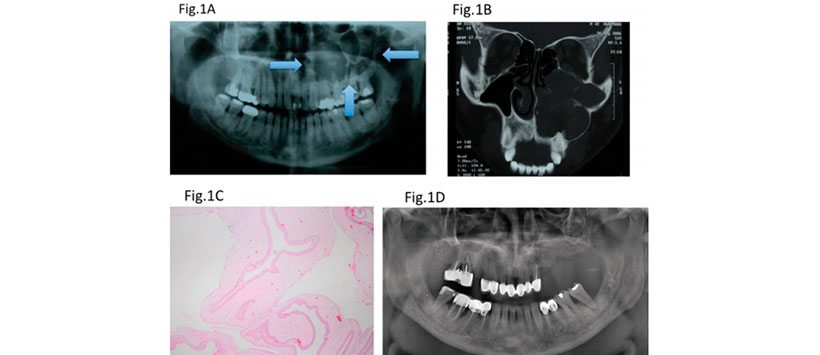

El objetivo de este estudio retrospectivo fue investigar la tasa de recurrencia de los queratoquistes odontogénicos (QCO) tratados mediante enucleación y ostectomía periférica. (Figura 2)